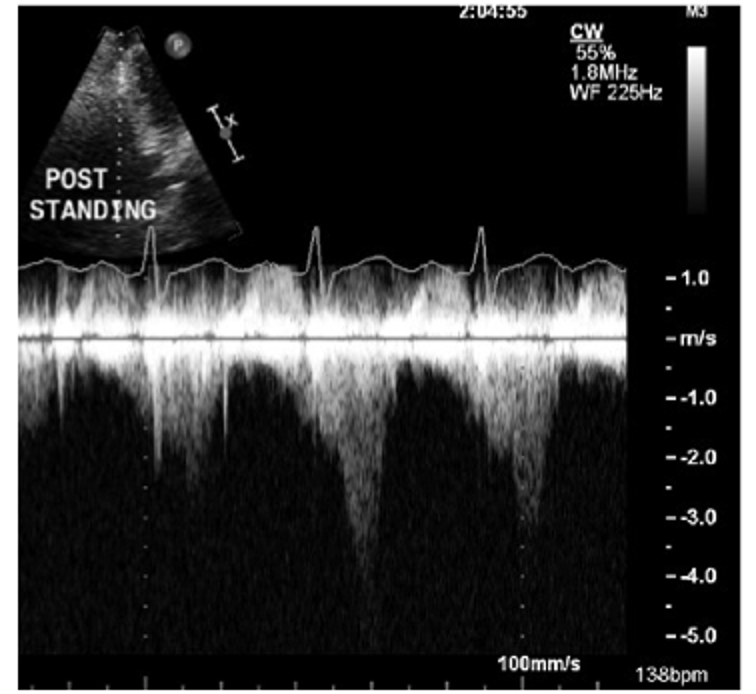

Dr. Harmony G. Reynolds and a research team are proving that OCT and cardiac MRI and can clarify why many women have heart attacks without coronary artery narrowing. Read the interview.